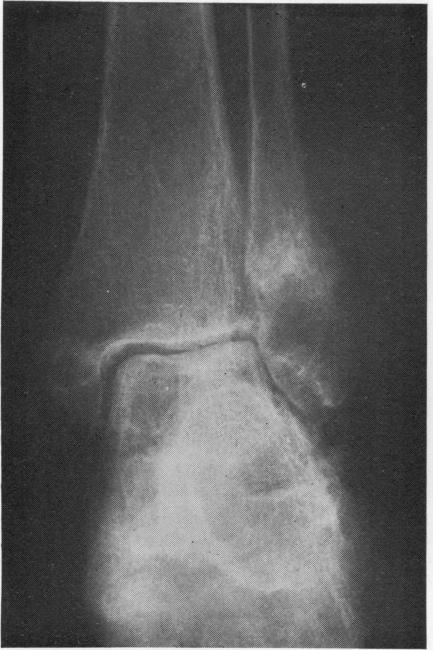

Fifty-four patients with rheumatoid arthritis and severe osteomalacia were found to have considerable bone and general deficiency problems. In 46 of them 14 stress fractures occurred and 32 minimal trauma fractures necessitating admission to hospital. Radiological abnormalities of absorption were found in nearly 25% of the total, implying that dietary factors alone are not always responsible for osteomalacia in patients with rheumatoid arthritis. A high index of suspicion is necessary in the diagnosis of osteomalacia in patients with rheumatoid arthritis, so they may benefit from treatment.